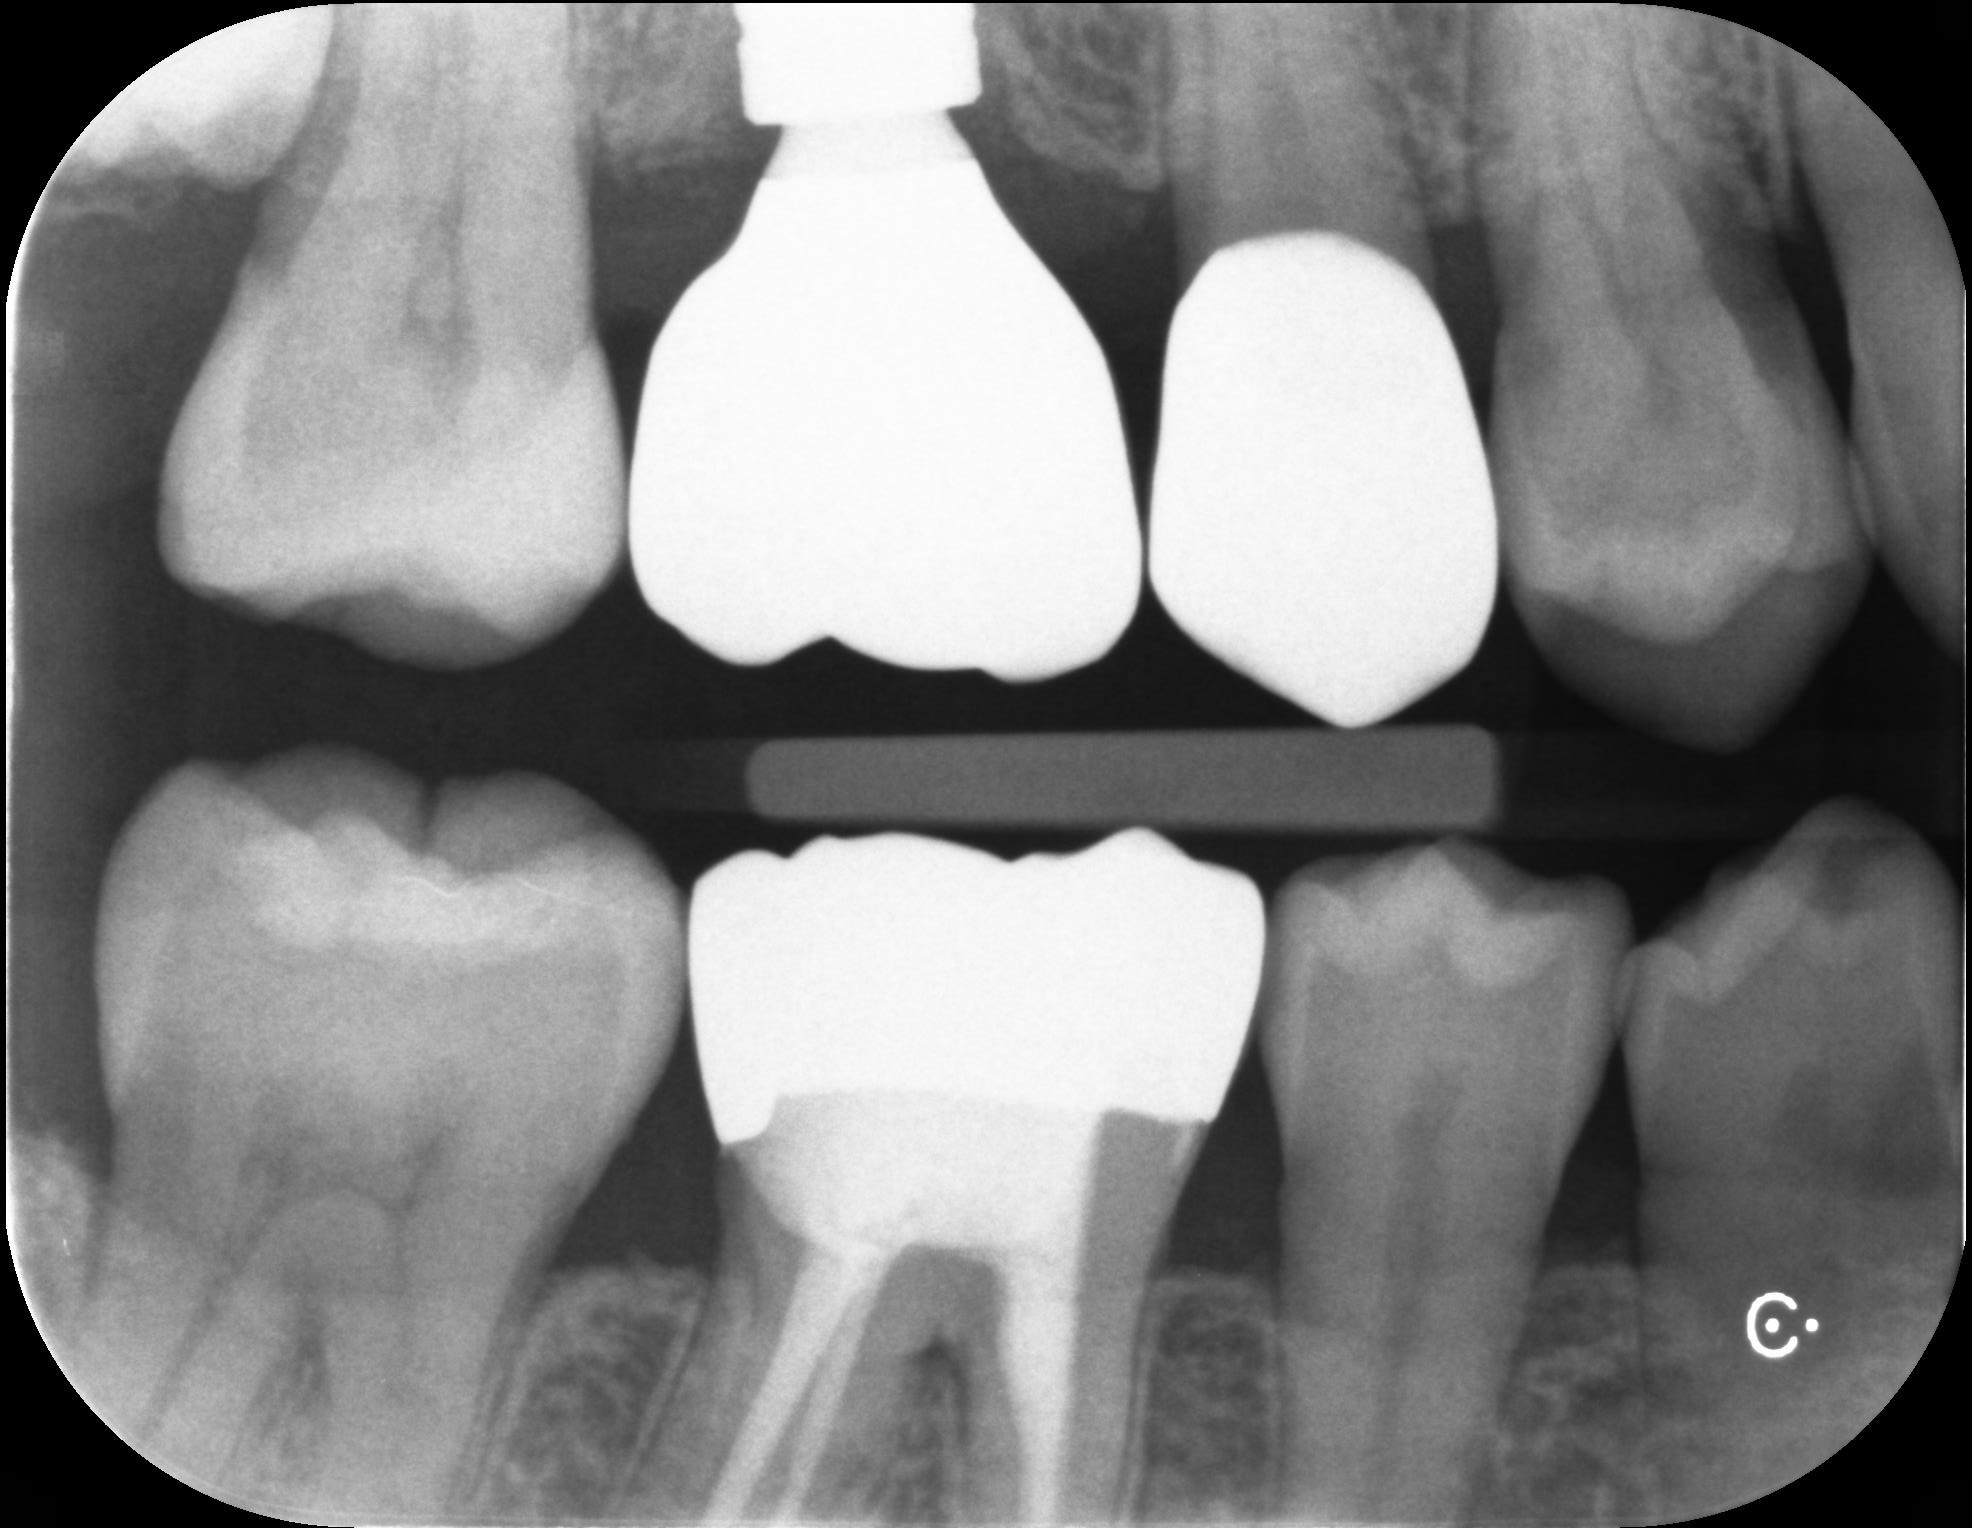

下記の写真は初診時から1年毎に撮影したレントゲンです。

写真の赤丸部分を見ていただくとわかるように、レントゲンで白く見えていた部分が黒くなってきていることがわかります。虫歯が大きくなってくると、このような変化がレントゲンで確認できるようになります。こういった変化を早期に捉え、最小限の治療介入で終わらせることが歯の長期予後につながります。

レントゲンはあくまで撮影した時点での切り抜きに他なりません。小さな虫歯があっても、2年前から同じ大きさなのであれば急いで治療をする必要性はありません。

規格性のあるレントゲン撮影は、必要のない治療を回避し、治療が必要な部分だけを早期介入するための重要な資料となります。

2025